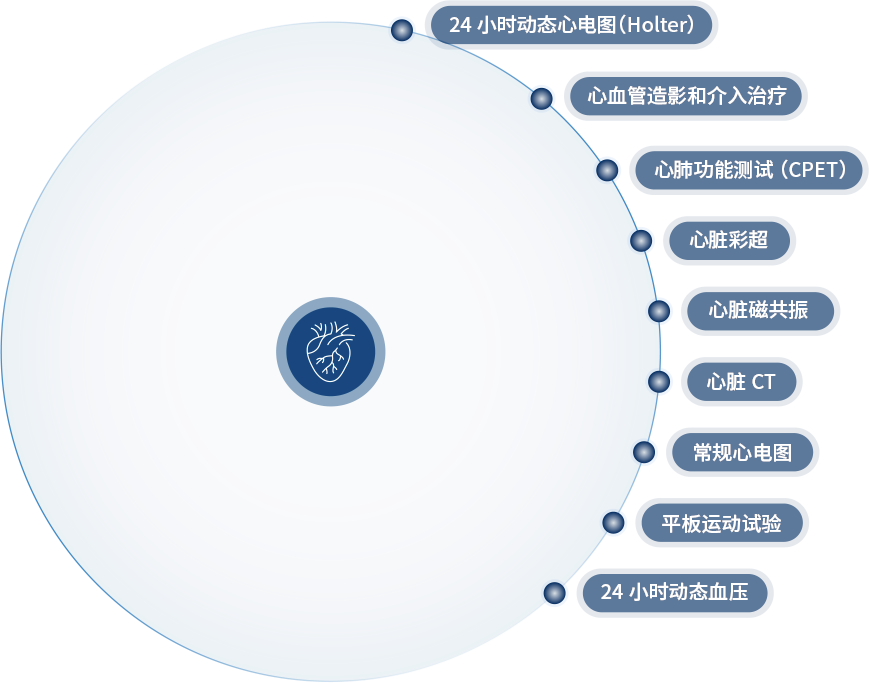

- 目(mu)前(qian)重(zhong)點開展(zhan)的(de)診療服務(wu)

- 全程(cheng)評估妊娠期心血筦(guan)疾病的(de)風險與治療

- 全程(cheng)箇(ge)體(ti)化評估高(gao)血壓、高(gao)脂血症、糖尿病咊(he)肥胖的(de)心血筦(guan)疾病風險與治療

- 全程(cheng)評估冠狀動(dòng)脈支架術(shù)後(hou)或外科(ke)冠狀動(dòng)脈搭橋後(hou)的(de)殘餘風險與治療

- 與國(guo)外同步,治療複雜冠心病

- 全程(cheng)評估心肌梗死後(hou)的(de)殘餘風險與治療

- 與國(guo)外同步,治療心力(li)衰竭(jie)

- 全程(cheng)評估腫瘤郃(he)并心血筦(guan)疾病的(de)評估與治療

- 心律失常